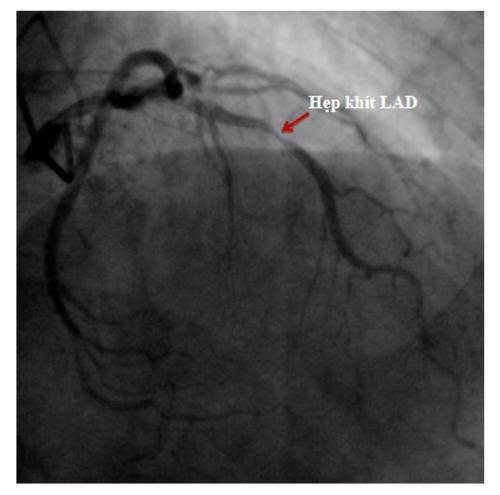

Nhiều bệnh nhân không có cơn đau tim rõ ràng, chỉ cảm thấy mệt, hụt hơi, tức ngực thoáng qua.

Tuy nhiên, khi kiểm tra chuyên sâu, bác sĩ phát hiện hẹp nặng động mạch vành LAD – nhánh mạch quan trọng nuôi tim.

👉 Với trường hợp này, đặt stent mạch vành kịp thời đã giúp tái thông dòng máu, giảm nguy cơ nhồi máu cơ tim và bảo vệ chức năng tim lâu dài.